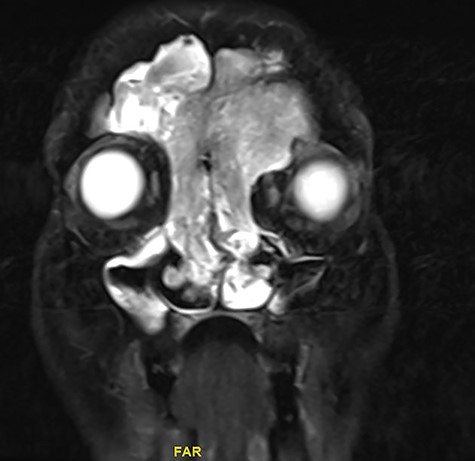

Magnetic resonance image (MRI) scanning also demonstrated a mass lesion involving both frontal and ethmoid sinuses, more into left FS causing expansion and rarefaction of the sinus wall, as well as extension of superior wall of left with extracoronal component causing mild proptosis. The lesion showed intermediate T2 signals with areas of high T2 signal along with postcontrast enhancement. No intracranial extension noticed (Figs 2 and 3).

Coronal MRI of paranasal sinuses, T1-weighted image post contrast.